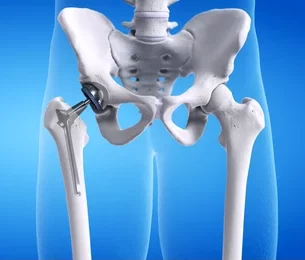

When the hip joint is very damaged and makes it hard to move normally, Hip Replacement surgery in Jaipur is done. The goal of surgery is to take out the worn-out joint surfaces and put in new ones that are stronger and allow for smoother, more stable movement. During the Process:

• Anesthesia is used during surgery to make sure the patient is comfortable and safe.

• The damaged femoral head (the ball of the hip joint) is carefully taken out.

• The hip socket is cleaned and ready for the artificial liner to be put in.

• A smooth metal stem with an artificial ball is put inside the thigh bone.

• A strong socket part is attached to the pelvic bone to put the joints back in their proper place.

• Before closing the incision, they check for stability, leg length, and joint movement.